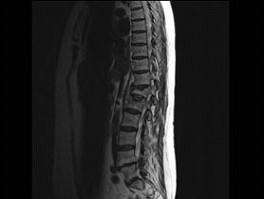

问题 男,65岁,背痛半月余,请结合影像学检查,选出最可能的诊断 ( )

选项 A、骨质疏松性椎体骨折 B、脊椎退行性变 C、脊柱转移瘤 D、化脓性脊柱炎 E、脊椎结核

答案 A